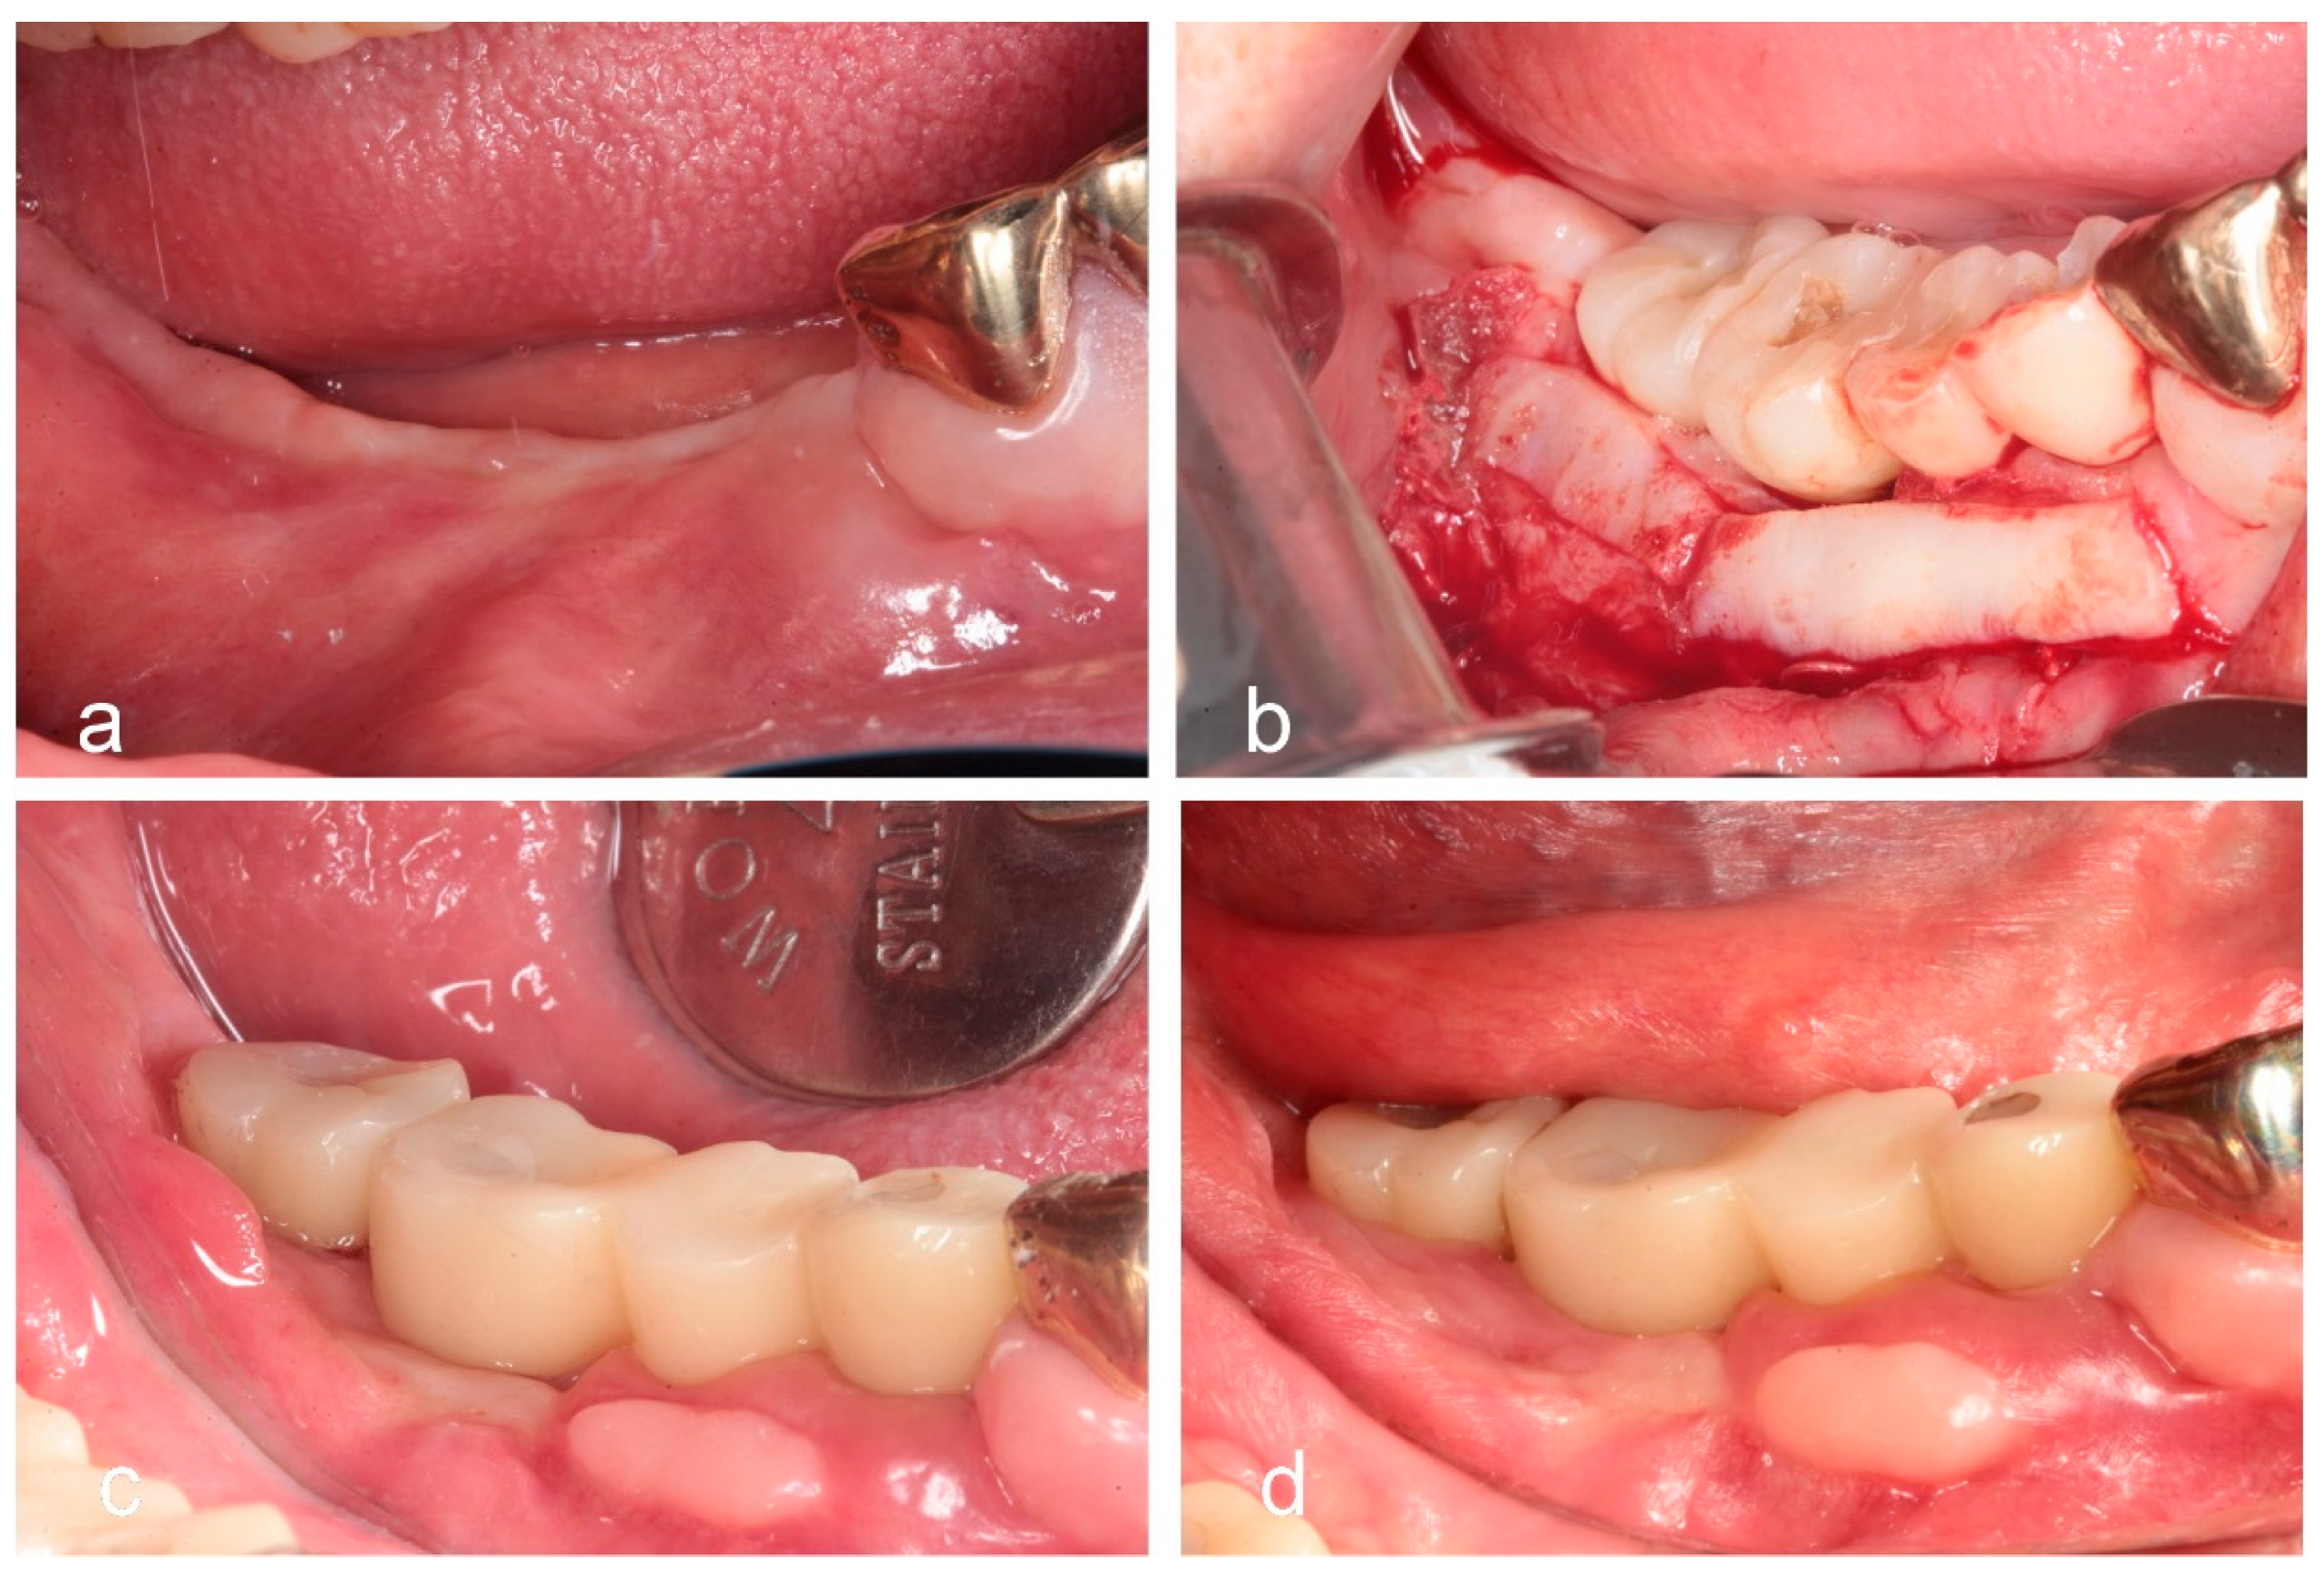

- Sohn, D.S. Reconstruction of three-dimensional alveolar ridge defects utilizing screws and implant abutments for the tent-pole grafting techniques. In Essential Techniques of Alveolar Bone Augmentation in Implant Dentistry, 2nd ed.; Tolstunov, L., Ed.; Wiley Blackwell: Hoboken, NJ, USA, 2023; pp. 404–418. [Google Scholar]

- Sohn, D.S.; Lui, A.; Choi, H. Utilization of tenting pole abutments for the reconstruction of severely resorbed alveolar bone: Technical considerations and case series reports. J. Clin. Med. 2024, 13, 1156. [Google Scholar] [CrossRef]